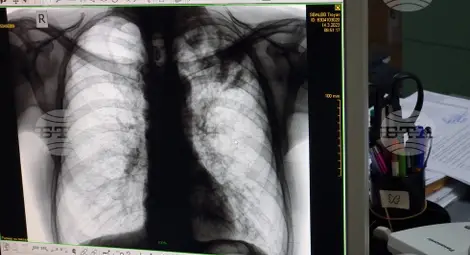

Безплатни прегледи за туберкулоза ще правят в МБАЛ "Д-р Иван Селимински" в Сливен

МБАЛ „Д-р Иван Селимински" организира периодично безплатни прегледи за туберкулоза, а последният скрининг бе през септември т.г. Заболеваемостта в област Сливен е над средната за страната.